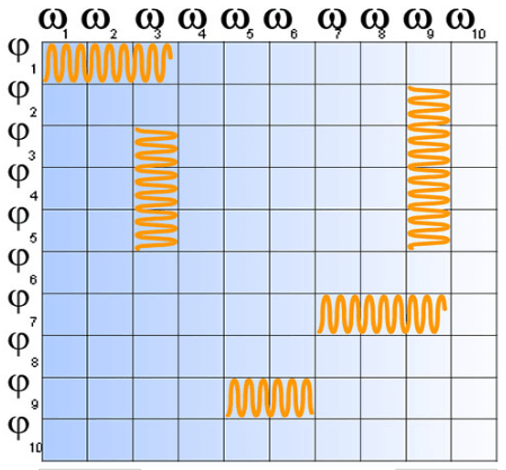

Matrix or Battleship

The signal is arranged in the matrix like the ships in a game of battleship. The system sorts information according to their phase and frequency. Just like the game of battleship where the ocean is a grid of letters and numbers, the MRI Fourier space is a grid of phase and frequency.

The K space is the frequential equivalent of the image which is a spatial representation. Example: We take one white square for which we decide to blacken every other box going toward the right and one out of 3 boxes going toward the bottom.

This process is repeated until We fill in the entire grid according to this rule. Consider the horizontal filling to be the phase and the vertical to be the frequency.

The space of the localization domain and frequency is referred to as “Fourier Space”. Fourier space is needed so that when the image is created from the data collected, the computer knows where each bit of information belongs. Similar to putting together a puzzle. If the pieces are not arranged in the exact order they were intended, the image will not look like the object it represents.

Filling the K Space

In most sequences, the Fourier space is filled in line by line: this is called linear filling. For other sequences, space is also filled in line by line but starting at the center: this is the centric mode. GE and Siemens scanners use this. Or Linear Low-High as it is called on Philips. This filling can also be done starting in the center but in a centrifugal manner or snail-shaped. This is centric elliptical mode common on GE or Siemens scanners or central as referred to on Philips.